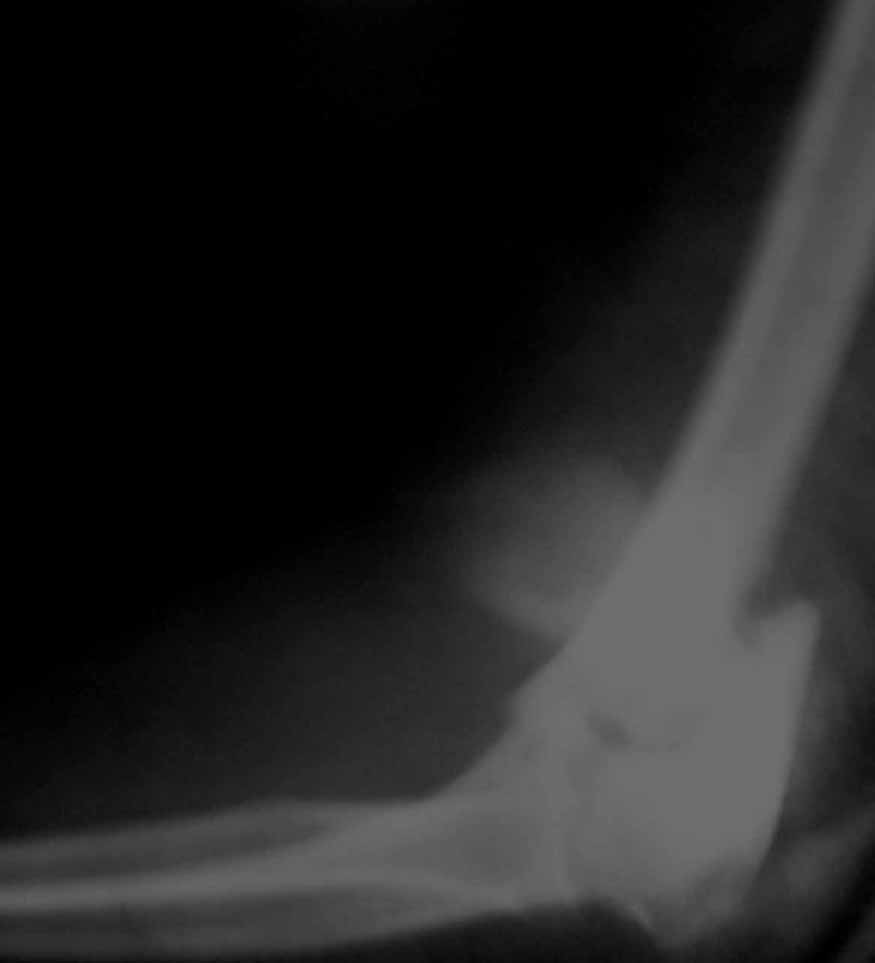

Женщина 42 лет, операция через неделю после перелома.

Д-з - открытый перелом мыщелков со смещзением и локтевой кости

без смещения - падение с лошади.

До операции снимки не очень, тем более в гипсе.

Остеосинтез закрытый (если так можно выразиться), т.е. без

разрезов. Длительность операции - около 1,5 часа со студентом.

6 щелчков ЭОПом.